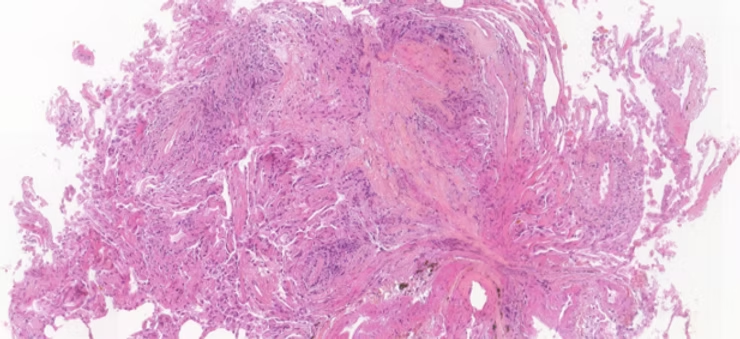

Une base de données unique de biopsies transbronchiques de patients greffés

L’hôpital Foch, principal centre de transplantation pulmonaire en France et l’un des meilleurs en Europe, a constitué une base de données inédite de plus de 2 500 lames numérisées d’anatomopathologie de biopsies transbronchiques de greffons pulmonaires, annotées par un panel international d’experts anatomopathologistes (États-Unis, Canada, France, Allemagne, Italie, Royaume-Uni, Pays-Bas) conformément à la grille LASHA “Lung allograft standardized histological analysis”.

Cette base de données a été mise à disposition sur la plateforme en ligne Trustii.io pour une durée de 2 mois, permettant ainsi à des équipes du monde entier de participer au challenge et de soumettre leurs modèles d’IA. Le but : créer un outil capable d'identifier des zones pathologiques dans les tissus pulmonaires de patients greffés.

La publication en open data offre un accès libre et gratuit à cette base de données inédite et ouvre la voie à de nouveaux travaux collaboratifs de recherche sur le rejet de greffe pulmonaire. Cette base de données de grande qualité et richement annotée constitue également un support pédagogique précieux pour la formation à l’analyse de lames d’anatomopathologie de biopsies pulmonaires.

Les modèles disponibles en open source sont accessibles et déployables partout dans le monde, rendant l’expertise en l’analyse des biopsies pulmonaires plus accessible et permettant la poursuite du développement d’outils d’aide au diagnostic dans le cadre des transplantations pulmonaires.